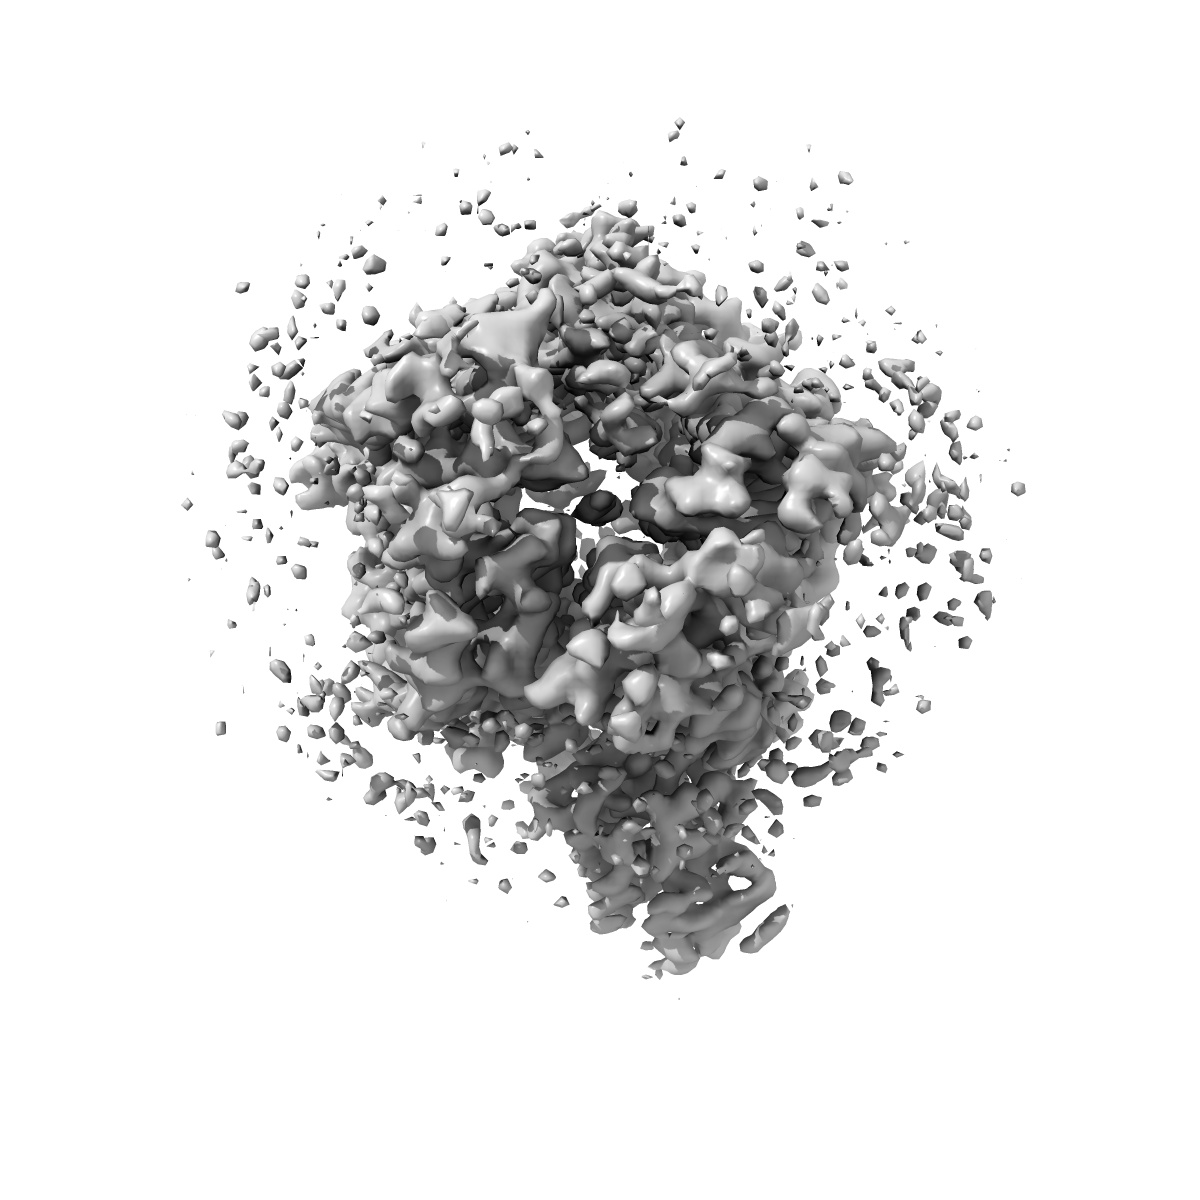

CryoEM structure of human full-length alpha1beta3gamma2L GABA(A)R in complex with diazepam (Valium), GABA and megabody Mb38.

Single-particle3.58 Å

Sample: Human full-length heteromeric alpha1beta3gamma2L GABA(A)R in complex with diazepam (Valium), GABA and megabody Mb38.

Fitted models: 6hup